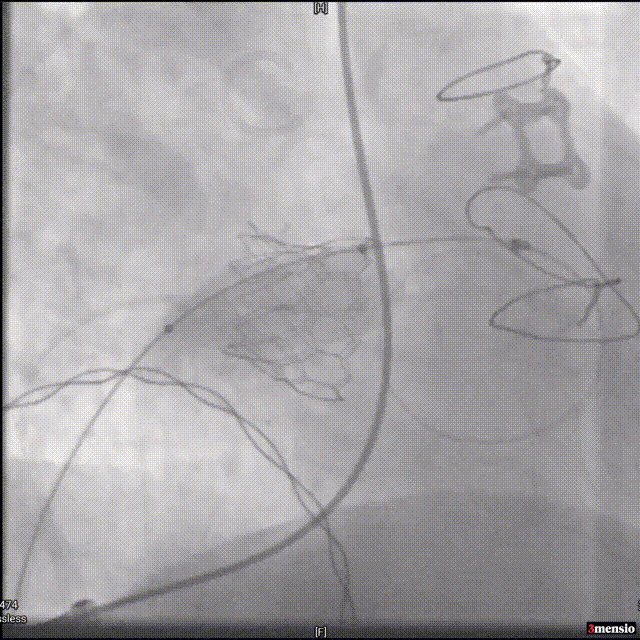

经造影明确原二尖瓣生物瓣位置,予以透视定位后,快速起搏使心率至180/分后缓慢充盈球囊至完全释放瓣膜;

瓣膜定位

瓣膜释放